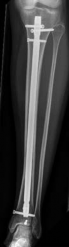

Nail Insertion and Distal Interlocking

Following meticulous preparation, the canal is reamed sequentially. Care must be taken not to over-ream the distal segment, which could compromise the already tenuous metaphyseal bone stock. The nail is inserted gently; forceful impaction is strictly avoided to prevent displacing the previously secured articular block.

Image

Distal interlocking must be maximized. The surgeon should utilize a minimum of three, and ideally four, distal locking screws, engaging the bone in multiple planes (e.g., two medial-to-lateral, one anterior-to-posterior). This multi-planar fixation is essential to control rotation and angular displacement in the wide metaphyseal bone.